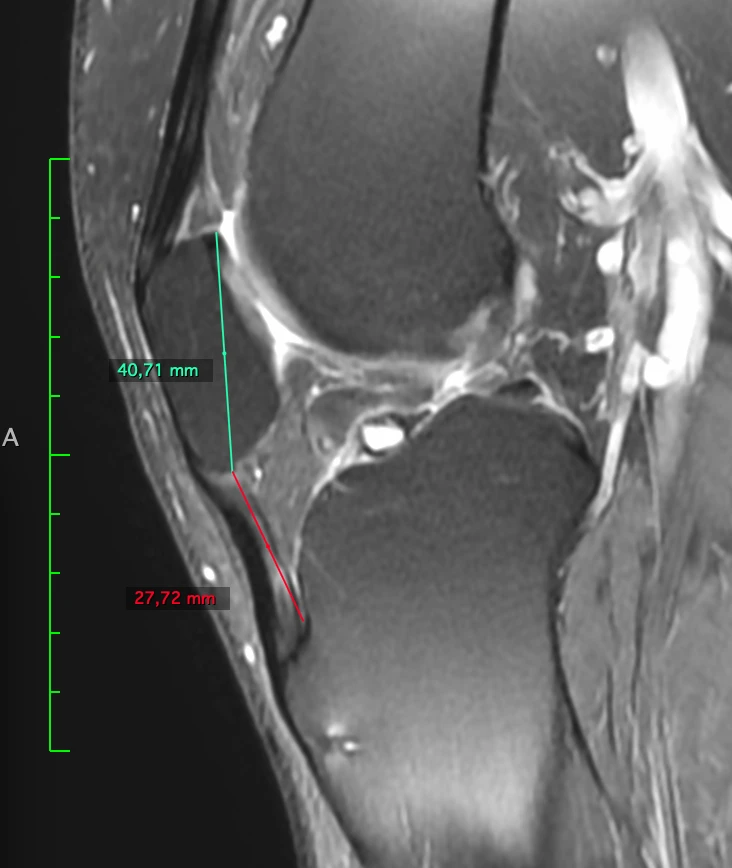

Patella baja и лигаментоз собственной связки надколенника вследствие этого.